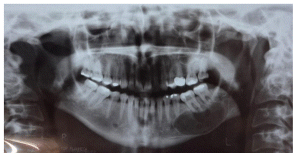

On 2006 A 47-year-old woman presented to the consultation and reported discomfort in the left mandibular area, in the panoramic x-ray a well-defined radiolucent area can be observed, apparently well encapsulated, which extends from the first premolar to the second molar with mobility grade one of the molars. An incisional biopsy was performed. The findings were semi-liquid content of yellowish, brown with pus content (Figure1).

Enucleation of the lesion and curettage of the area were performed, as well as a endodontic treatment of the second premolar, first and second lower left molar. The patient remained stable for 6 years when a panoramic rx was taken on 03/13/2012 as a control (Figure 2).

Subsequently, seven months later, on 10/17/12, she presented endodontic problems in the previously treated teeth and lost the second lower left molar after the revision, radiographic changes were seen in the panboramic X ray. (Figure 3) An incisional biopshy was taken,10 months 15/08/2013 based on the diagnosis of the biopsy, a CT scan was taken and a stereolithography model was developed for the surgery of the central ossifying fibroid by mandibular resection.